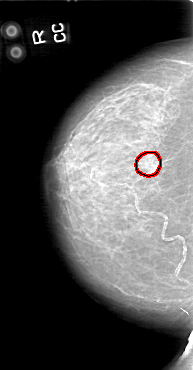

D_4044_1.RIGHT_CC

RIGHT_CC LINES 5176 PIXELS_PER_LINE 2701 BITS_PER_PIXEL 12 RESOLUTION 43.5 OVERLAY

FILE: D_4044_1.RIGHT_CC.OVERLAY

TOTAL_ABNORMALITIES 1

ABNORMALITY 1

LESION_TYPE CALCIFICATION TYPE COARSE DISTRIBUTION CLUSTERED

ASSESSMENT 0

SUBTLETY 5

PATHOLOGY BENIGN

TOTAL_OUTLINES 2